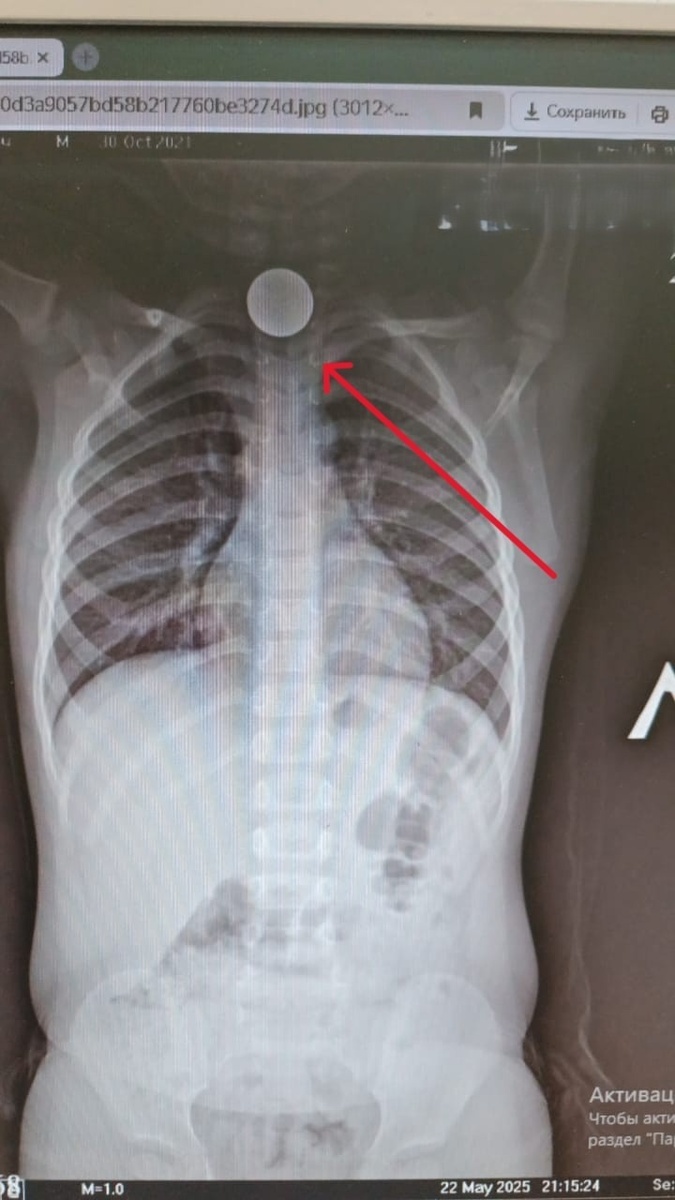

В Башкирии трехлетний ребенок проглотил монетку

В Мечетлинском районе 3-летний мальчик проглотил монетку — она застряла в пищеводе. Было принято срочное решение — эвакуировать ребёнка в Уфу для оперативного извлечения инородного тела.

В Мечетлинском районе 3-летний мальчик проглотил монетку — она застряла в пищеводе.

Было принято срочное решение — эвакуировать ребёнка в Уфу для оперативного извлечения инородного тела.